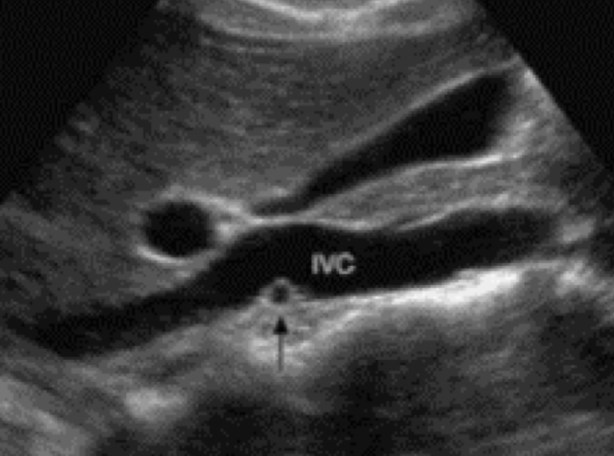

?invasion of the renal vein and IVC

RCC can invade what vessels?

renal vein and IVC